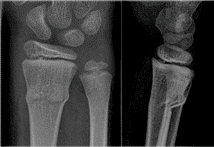

Greenstick and buckle fractures

- Buckle fractures occur when the thin cortex buckles under the force of a fall, but no displacement occurs, and continuity of the cortex is not disrupted.

- Greenstick fractures occur when a force breaks one cortex, but the other remains intact and acts as a hinge.